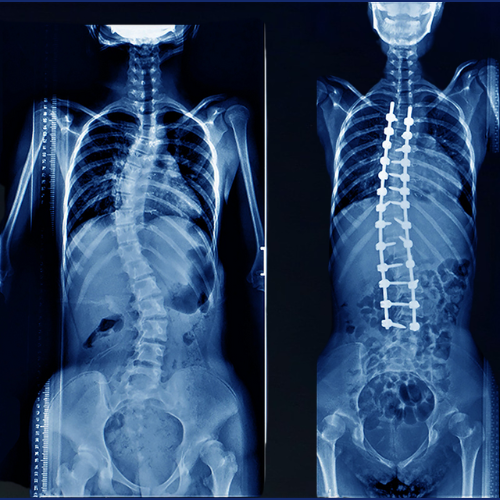

Scoliosis Surgery

Scoliosis is an abnormal sideways curvature of the spine that can occur in children, adolescents, or even adults. Without timely treatment, scoliosis may leadRead More